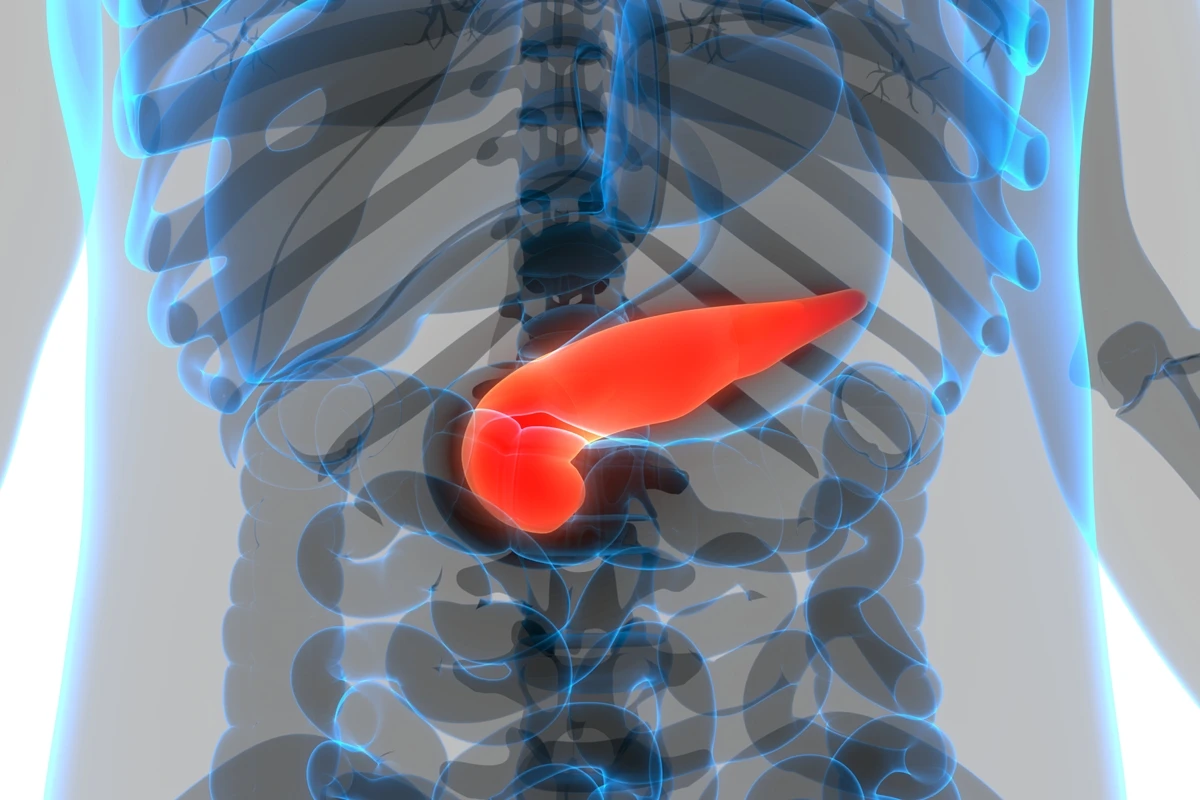

Embora não seja muito lembrado, exceto quando algo vai mal, o pâncreas é um órgão fundamental para a saúde e bem-estar do corpo como um todo. Segundo a nutricionista Juliana Andrade, colunista do Metrópoles, ele “produz enzimas digestivas e hormônios como a insulina, responsável por controlar a glicose no sangue”.

Não cuidar da região corretamente pode gerar consequências como diabetes tipo 2, pancreatite e até aumento do risco de câncer pancreático. E você sabe quais alimentos têm efeito contrário, ou seja, preservam a saúde do pâncreas? Tome nota!